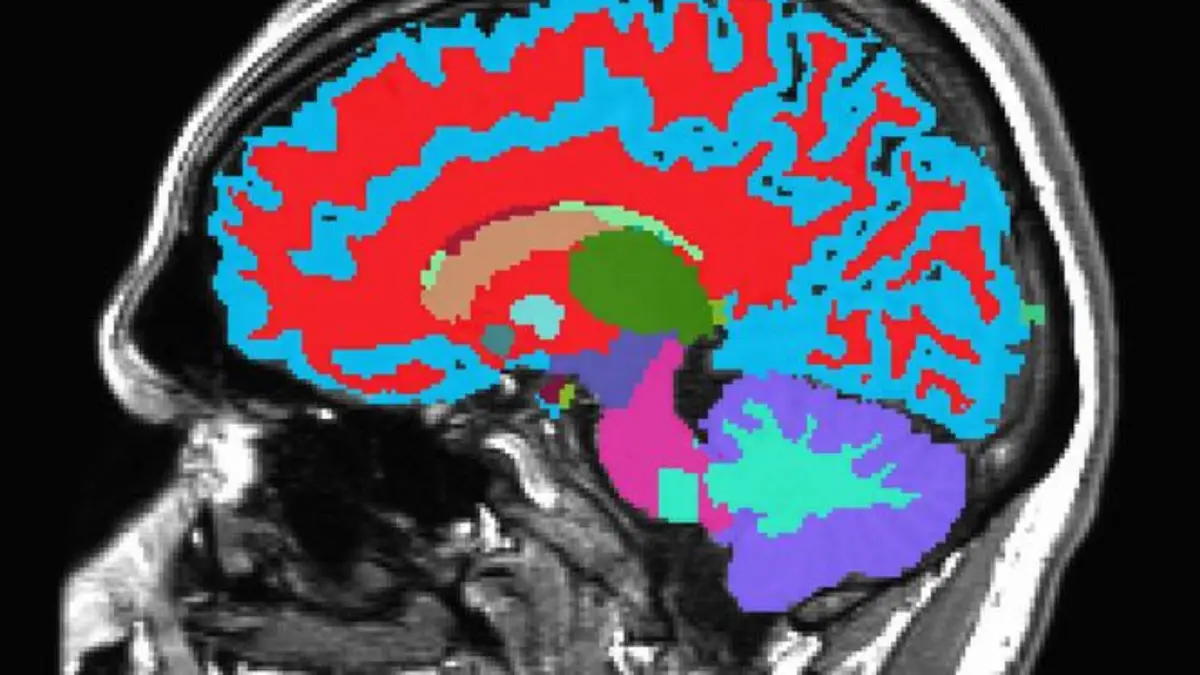

Alat Baru Prediksi Penuaan Otak dengan Satu Pemindaian MRI

Mengembangkan alat yang dapat memperkirakan kecepatan penuaan biologis seseorang menggunakan satu kali pemindaian MRI otak untuk membantu memprediksi risiko penyakit kronis dan memperpanjang kualitas hidup.

Para peneliti dari Duke, Harvard, dan University of Otago mengembangkan alat bernama DunedinPACNI yang dapat memperkirakan seberapa cepat seseorang menua secara biologis hanya dengan menggunakan satu kali pemindaian MRI otak.